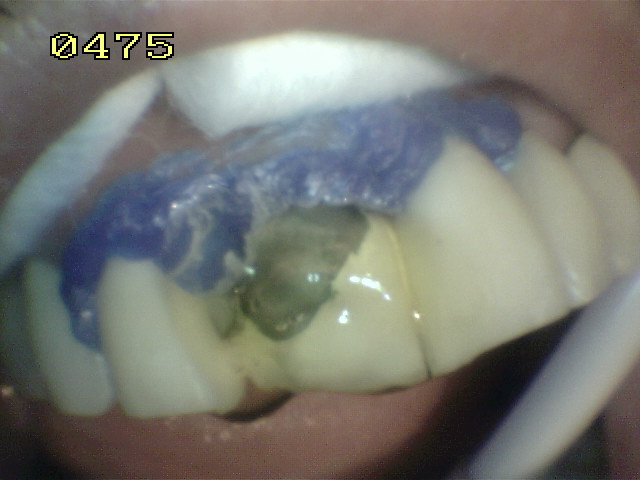

Aspecto del grabado del metal y porcelana Se utilizo silano y adhesivo para resina.  Opacificador de metal   y resina microhibrida A3